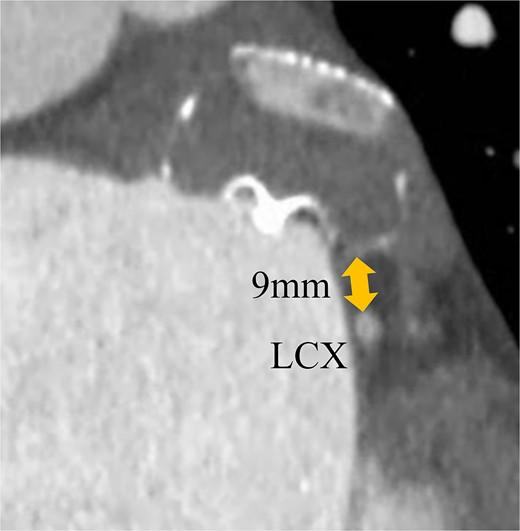

A 74-year-old male with a history of chronic atrial fibrillation (AF) for over 10 years, cardioembolic stroke, and cerebral hemorrhage, who had undergone LAA closure using the WATCHMAN device 1 year prior, was admitted after a follow-up contrast-enhanced CT scan revealed a 25-mm intracardiac mass in the right atrium (RA) (Fig. 1). After the WATCHMAN implantation, the patient was initially on direct oral anticoagulant (DOAC) but switched to dual antiplatelet therapy (DAPT) following the placement of a drug-eluting stent during percutaneous coronary intervention performed 9 months later. Transthoracic echocardiography revealed a left ventricular ejection fraction of 61% and a right atrial mass measuring 17 × 19 mm with slight mobility (Fig. 2). Despite anticoagulation therapy with heparin, the right atrial mass did not reduce in size. The patient decided to undertake surgical removal of the mass due to the potential risks of tumor or embolization. Additionally, contrast-enhanced CT showed a peri-device leak around the WATCHMAN device (Fig. 3). Considering the patient’s history of cerebral hemorrhage and the anticipated future cessation of anticoagulation therapy, we determined to perform WATCHMAN device explantation and LAA closure. Preoperative contrast-enhanced CT showed no thrombi attached to the WATCHMAN device and sufficient distance from the left circumflex artery (LCX) and the device (Fig. 4). We planned to remove the device by incising from the outside surface of the LAA. The Maze procedure was not performed because it was considered less effective due to the patient’s history of AF lasting more than 20 years and the presence of flat f-waves in lead V1 on the 12-lead electrocardiogram.

Preoperative enhanced computed tomography imaging showing the distance between the WATCHMAN device and the LCX was ~9 mm.